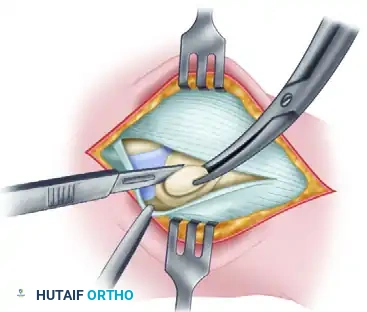

Step 3: Excision of the Accessory Navicular

Using a scalpel or a small osteotome, sharply dissect the accessory navicular free from its soft tissue attachments, including the anomalous insertion of the PTT. Shell the ossicle out of its bed.

Figure 82-39C: Removal of the accessory navicular.